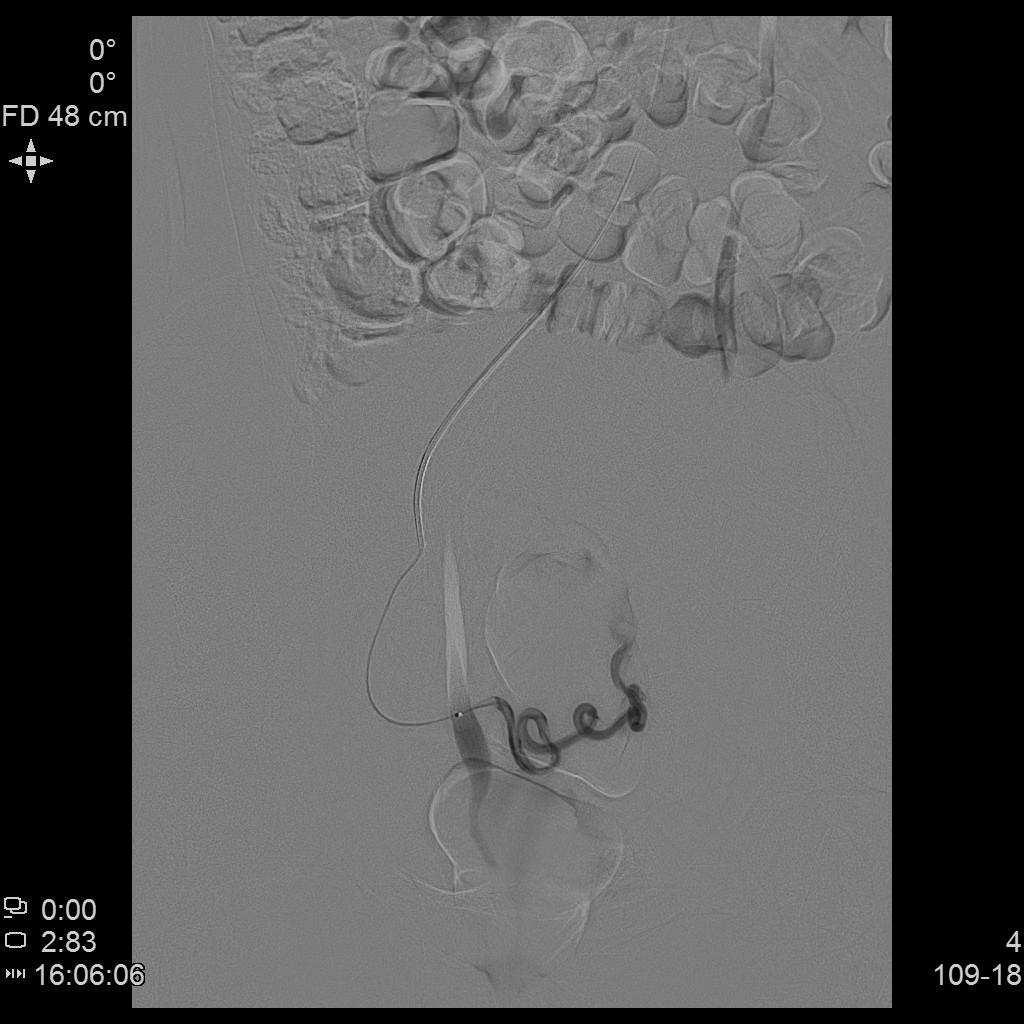

- 微导管进一步超选插管右侧子宫动脉主干造影确认位置。

右侧子宫动脉造影

- 微导管进一步超选插管左侧子宫动脉主干造影确认位置。

左侧子宫动脉造影